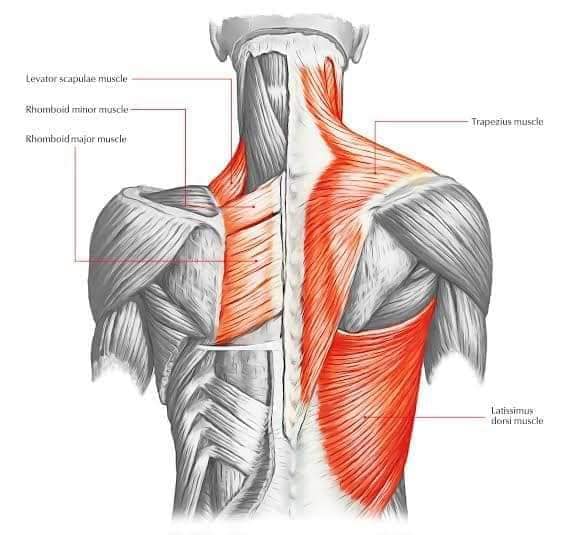

Спинні м'язи

Спинні м'язи виконують функції підтримки хребта, а також дозволяють здійснювати рухи тулуба.

Поверхневі спинні м'язи

М'язи, що піднімають лопатку: Трапецієподібний м'яз: великий м'яз, що покриває верхню частину спини. Його функція - підтримка і рух лопаток, а також забезпечення стабільності хребта.

М'язи, що ведуть лопатку до хребта: Широкий м'яз спини: великий м'яз, що розташований в нижній частині спини. Він відповідає за рухи плечей і лопаток, а також за розширення верхньої частини тулуба.

Глибинні спинні м'язи

М'язи, що забезпечують стабільність хребта: М'язи, що розташовані між хребцями: включають мускулатуру, яка забезпечує стабільність і підтримку хребта, а також дозволяє здійснювати рухи хребта.

М'язи, що здійснюють ротацію та нахили

М'язи, що забезпечують ротацію хребта: Ротаційні м'язи: допомагають у здійсненні обертальних рухів тулуба, а також у підтримці рівноваги і стабільності хребта.